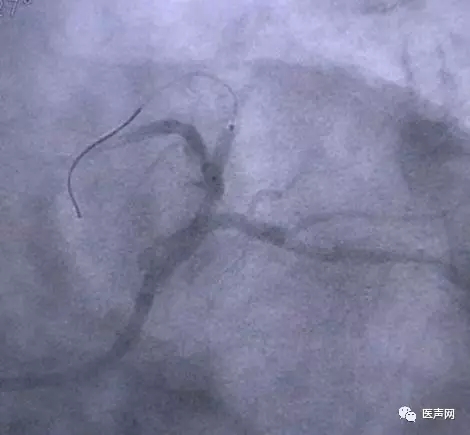

病例8:对角支开口病变-近端病变

CAG:对角支开口病变-近端病变,为小血管病变

JL4GC deep seating, 悬空作业(有时Dr. Yu双导丝,保护LAD,亦作标记)。 Yukon DES 2.0×12mm DES,12bar, 20sec扩张释放。

· 支架张开后,导丝继续向远端(支架支撑技术)。

· 导引导管亦可在导丝+球囊支撑下勾住左冠。

对初学者来说,这种在导引导管支撑不好的前提下,悬空作业,有一定难度及风险,可双导丝(再入LAD),或更换更好GC,或预扩来完成。因为Dr.Yu 多 直接支架术(direct stenting)。今天总的来说,虽然病变不是非常复杂,但比较过瘾。有临床试验,TAX. DE study,DCB-ISR-study, VB CTO, Yukon polymer-free DES等,还有许多小技巧。关键是明白导管的精髓,导管室的主旨所在。